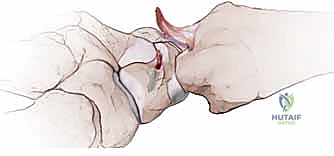

3. Creation of the Dorsal Capsular Flap

Now we focus on the dorsal capsule itself, which will form the basis of our capsulodesis.

• Flap Design: We need to create a robust, rectangular capsular flap. The dimensions are critical: approximately 25 mm long and 10 mm wide.

• Proximal Incision: We make a transverse capsular incision just proximal to the vascular dorsal carpal arch. This arch typically runs transversely across the dorsal aspect of the carpus. By staying proximal to it, we ensure the blood supply to our flap is preserved.

• Flap Elevation: Using a small periosteal elevator and careful sharp dissection with a #15 blade, we elevate the tissue in a distal-to-proximal direction. The key is to keep the flap thick and full-thickness, incorporating all layers of the dorsal capsule. We meticulously dissect it off the underlying carpal bones (scaphoid, lunate, capitate).